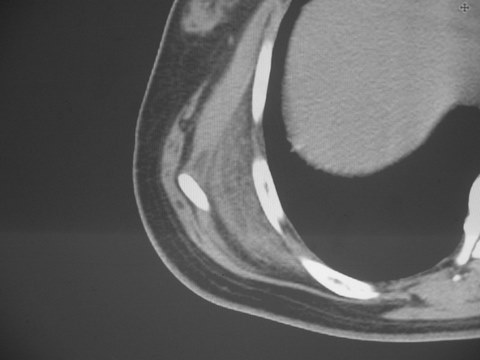

无意中发现右背部肩胛下缘半球状突起,无红,热,痛感觉。拍平片未见异常。ct发现右肩胛下角深层新月型软组织肿胀,ct值-50至15,大家看看是什么性质,来源,初步考虑来源于下后锯肿,考虑下后锯肌肿胀,可是病人无明确外伤史,也不疼痛

典型的弹性纤维瘤,从部位\\形态\\密度来看均极典型.现引用lzdyjg老师的点评:

三、弹性纤维瘤影像

典型位于背部,在肩胛下角和胸壁软组织之间,肿瘤表面为菱形肌和背阔肌所被覆深部,紧邻肋骨和肋间肌,呈半圆形或扁豆状,宽基底与胸壁相交,边界比较清楚,相邻的肌肉和肋骨无侵蚀,部分病变与其表面的临近肌肉之间可受压呈弧形的脂肪界面,肿瘤周围软组织无水肿。

从mr表现可以推断ct影像,即肿块呈软组织密度,病灶内可出现脂肪密度的低密度影。